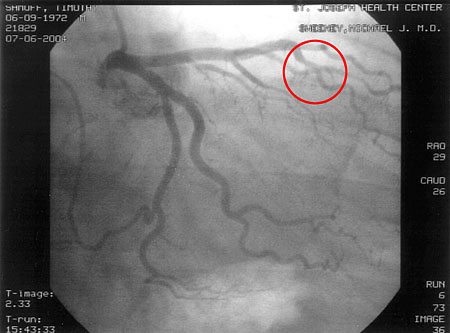

10 soruda anjiyo nedir ve nasil yapilir anjiyo stent